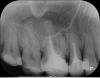

ОльгаВМ Опубликовано 5 ноября, 2012 Поделиться Опубликовано 5 ноября, 2012 Уважаемые доктора,интересует ваше независимое мнение о состоянии пломбировки корней.Я бы хотела поставить коронки на 15, 16 и 26, 27 (верхняя челюсть). Нужно ли перелечивать каналы ? Есть ли там воспаление? Ссылка на комментарий

DokDent Опубликовано 5 ноября, 2012 Поделиться Опубликовано 5 ноября, 2012 Надо перелечивать каналы в этих зубах,менять пломбы в 1.8;1.4 и лечить 1.7 Ссылка на комментарий